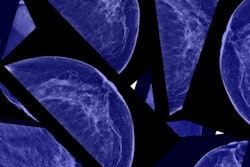

Breast cancer screening with digital mammography is effective at finding life-threatening cancers early without increasing recall rates, according to a study published December 11 in Radiology. The findings offer further evidence of the benefits of routine screening mammography.

"Our study clearly shows the benefits of digital mammography in terms of overall cancer detection rate -- and that this benefit is achieved without an increase in recall rates," said lead author Roger Blanks, PhD, of the Nuffield Department of Population Health at the University of Oxford. "This finding is particularly important as digital images provide increased visualization for features associated with cancers such as high-grade ductal carcinoma in situ [DCIS] and grade 1 and grade 2 invasive cancers."

Digital mammography increased the overall cancer detection rate by 14%, compared with film-screen mammography, and digital mammography also found more invasive cancers, according to the researchers. In addition, among women between the ages of 45 and 52 undergoing their first breast cancer screening exam, digital mammography increased the cancer detection rate by 19%. Among women between the ages of 53 and 70, the incident cancer detection rate increased by 13%.